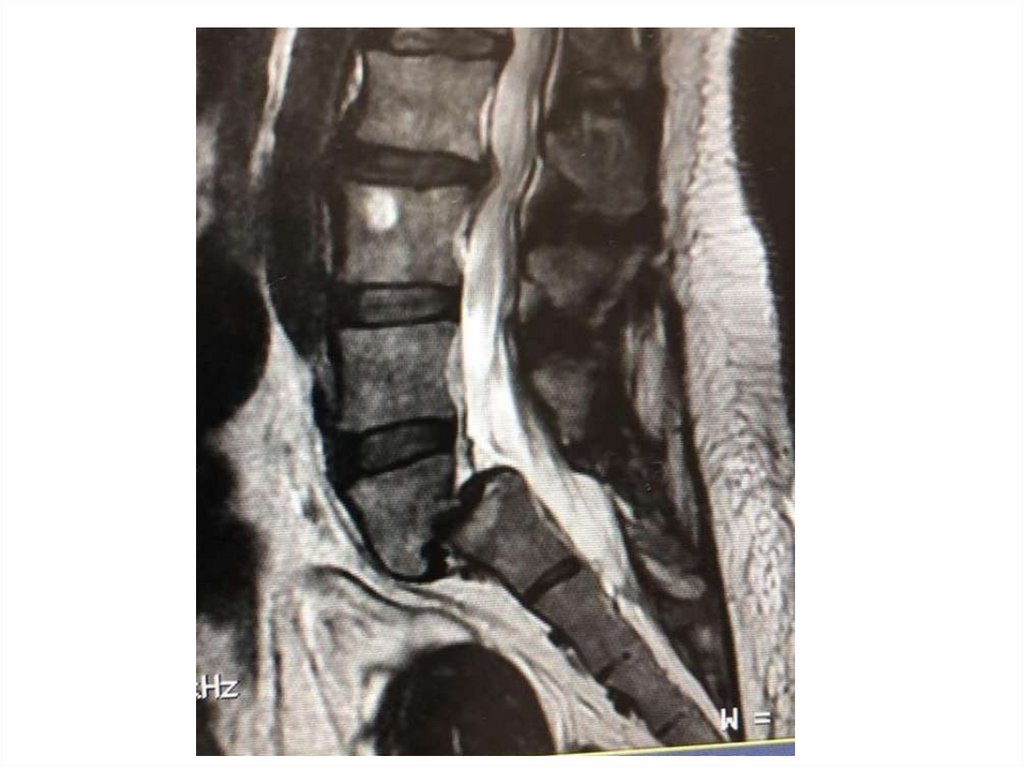

МРТ при переломах

позвонков

КТ и МРТ при переломе позвонков

• Состояние спинного мозга